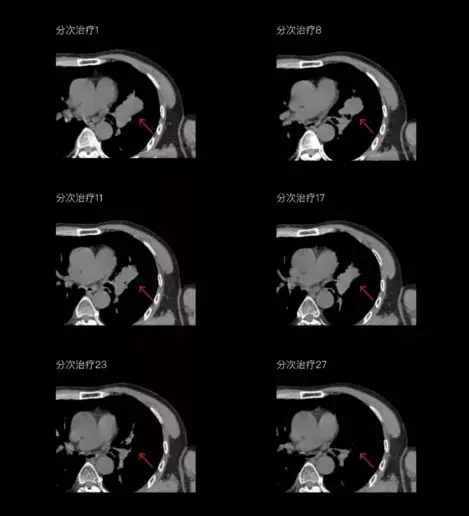

聯(lián)影CT-linac全程監(jiān)測治療過程病灶的變化,及時調(diào)整和優(yōu)化治療方案

一體化CT-linac讓自適應(yīng)放療ART概念變?yōu)楝F(xiàn)實(shí)?;颊呷煶虪顟B(tài)監(jiān)控,適時在線調(diào)整治療計劃,精準(zhǔn)控制治療劑量,為患者動態(tài)定制個體化治療方案。uAI賦能智能勾畫和自動計劃,秒級勾勒靶區(qū)和危及器官,大幅縮短自適應(yīng)放療時間。